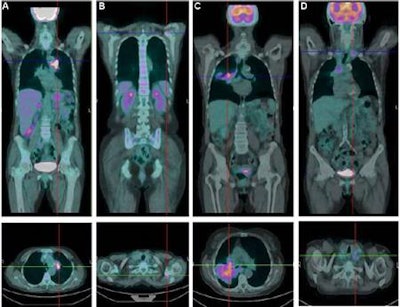

Using FDG-PET/CT, researchers in Italy have found a correlation between cell-free tumor DNA circulating in the bloodstream and the aggressiveness of tumors in patients with advanced non-small cell lung cancer (NSCLC), according to a study published in the November issue of the Journal of Nuclear Medicine.

Lead study author Dr. Silvia Morbelli, PhD, from the IRCCS San Martino-IST National Cancer Research Institute in Genoa, and colleagues suggest that cell-free DNA might better reflect the biological behavior and aggressiveness of tumors than tumor burden in metastatic NSCLC (JNM, November 2017, Vol. 58:11, pp. 1764-1769).

The study included 24 men and 13 women between the ages of 51 and 80 years who had never been treated with chemotherapy. Morbelli and colleagues found a direct correlation between the amount of cell-free DNA and tumor metabolism -- but not with metabolic tumor volume.

The researchers also reported that a subgroup of 13 patients with metabolically active bone lesions had higher levels of cell-free DNA. While cell-free DNA correlated with tumor metabolism, no association was found with circulating tumor cells.